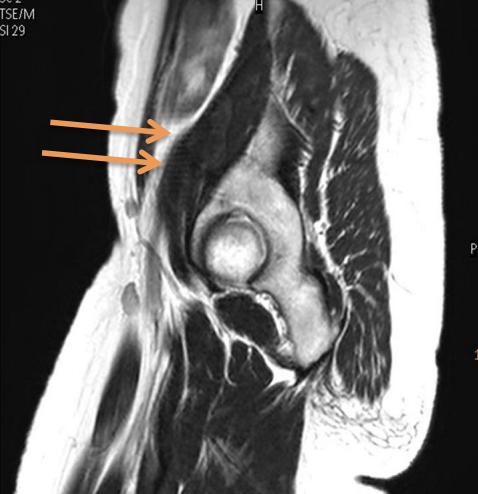

magic angle arttifact occurs when

a tendon or ligament is positioned approximately 55° to the direction of the main magnetic field, and a short TE value pulse sequence is utilized., sometimes longer flip angles

confirmation of magic angle artifact

confirmation of magic angle artifact, instead of tendinopathy, is made by the utilization of a long TE sequence, where the long T2 relaxation time of the collagen fibers will not yield high signal in the tendon at the 55° angle to the magnet.